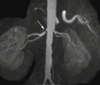

What pathology is shown on this MRA?

Renal artery stenosis